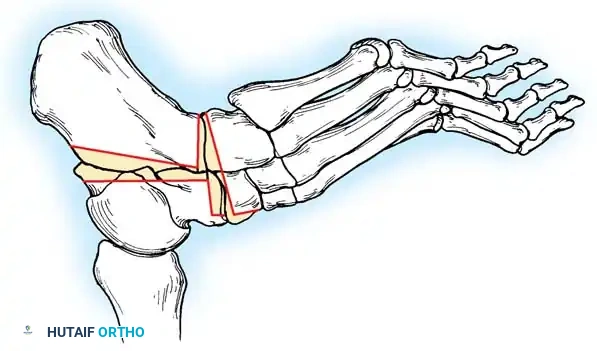

* Joints Included: Subtalar, talonavicular, and calcaneocuboid joints.

* Technique: Extensive medial and lateral approaches are required. Aggressive biplanar wedge resections are necessary to correct the rigid varus and midfoot cavus. The joints are rigidly fixed with large-fragment screws and anatomic plates.

* Caveat: While powerful, triple arthrodesis sacrifices hindfoot motion and increases stress on the ankle joint, potentially accelerating ankle osteoarthritis in the long term.